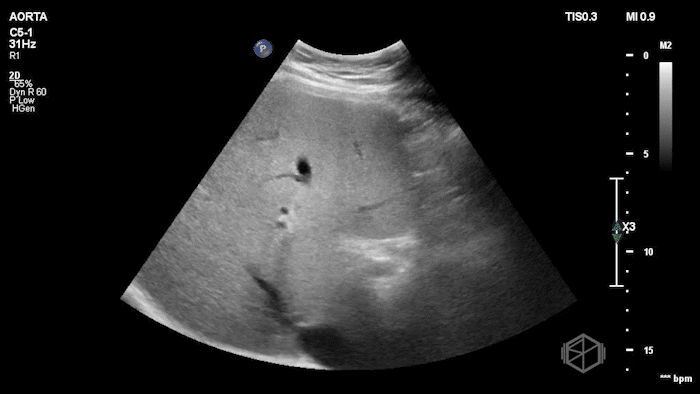

Their POCUS is below:

The POCUS demonstrated a thickened, edematous gallbladder wall with tumefactive sludge and gallstones, concerning for acute cholecystitis, though an underlying mass could not be excluded. A CT scan was obtained, which showed a layering gallstone versus gallbladder polyp, gallbladder wall edema, and possible pericholecystic fluid.